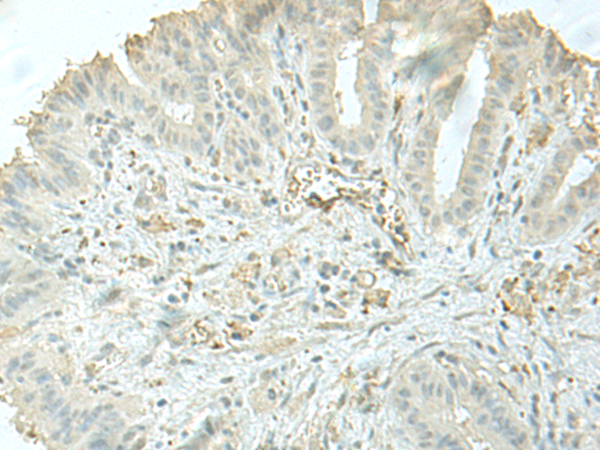

IHC positive control: |

Human gastric cancer and Human thyroid cancer |

IHC Recommend dilution: |

40-200 |